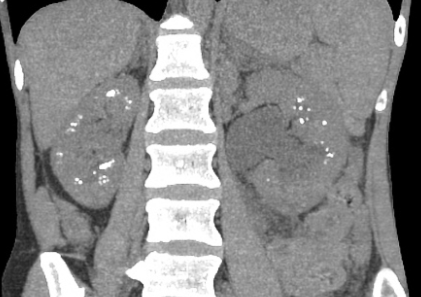

Maladie de Cacchi-Ricci

- Calcifications de la médullaire → Finit en Néphrocalcinose médullaire

- Dilatation des tubules: aspect “paintbrush” du contraste urinaire